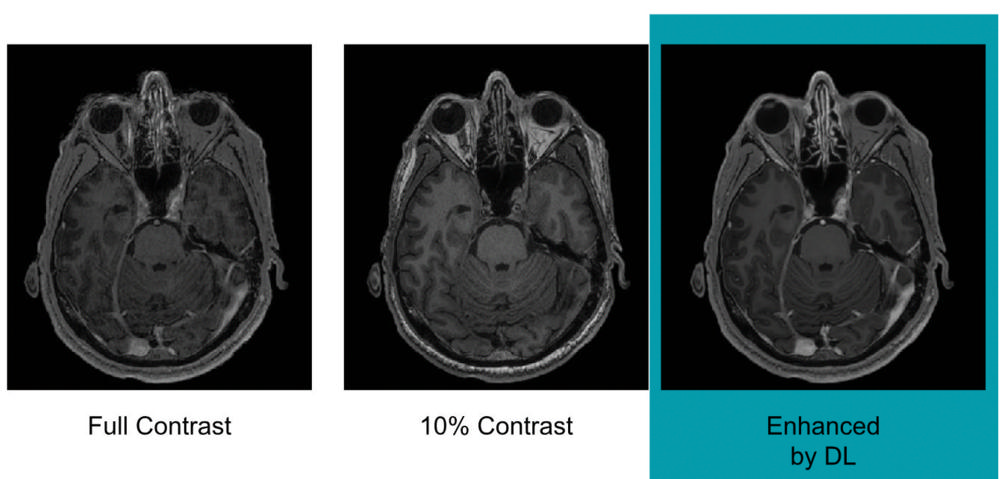

To train the deep learning algorithm, the researchers used MR images from 200 patients who had received contrast-enhanced MRI exams for a variety of indications. They collected three sets of images for each patient: pre-contrast scans, done prior to contrast administration and referred to as the zero-dose scans; low-dose scans, acquired after 10 percent of the standard gadolinium dose administration; and full-dose scans, acquired after 100 percent dose administration.

The algorithm learned to approximate the full-dose scans from the zero-dose and low-dose images. Neuroradiologists then evaluated the images for contrast enhancement and overall quality.

Results showed that the image quality was not significantly different between the low-dose, algorithm-enhanced MR images and the full-dose, contrast-enhanced MR images. The initial results also demonstrated the potential for creating the equivalent of full-dose, contrast-enhanced MR images without any contrast agent use.

Figure 1. Example of full-dose, 10 percent low-dose and algorithm-enhanced low-dose.